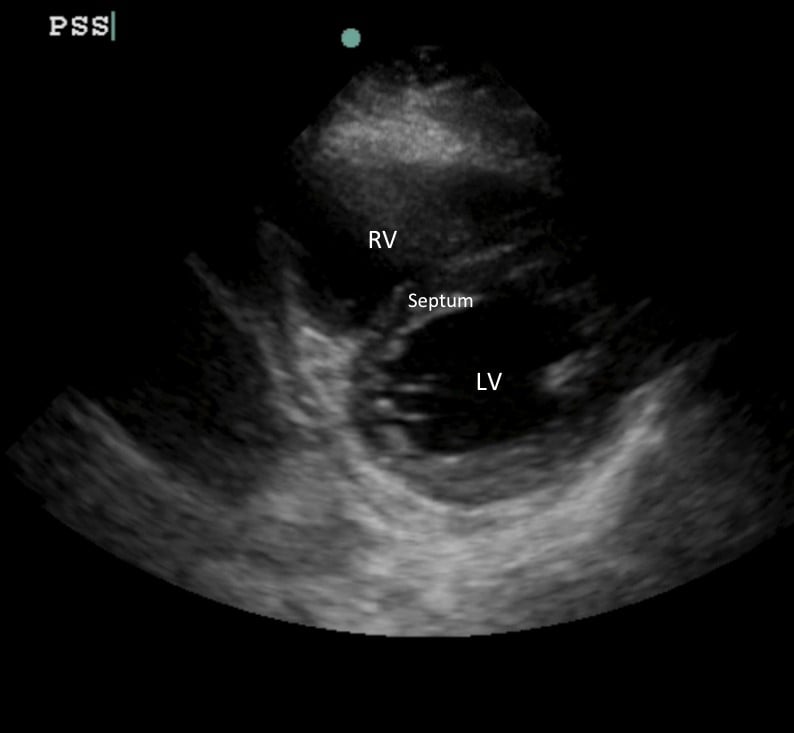

画像1:正常な三日月状のRVと同心円状のLV